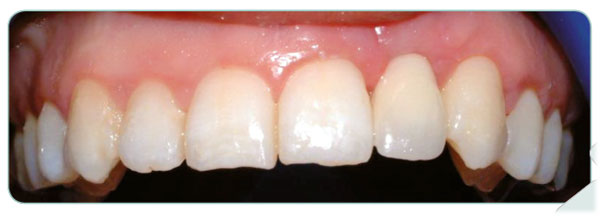

Our patient has now a hollywood stile smile after application of teeth whitening and four composit laminate veneers to fill the gaps between her teeth. During the treatment none of the teeth got a single damage.